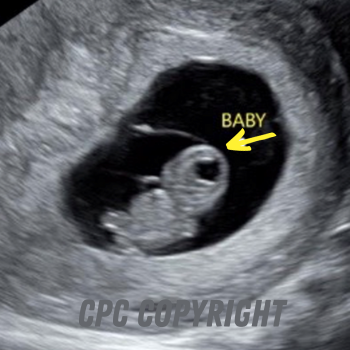

5 weeks after conception/ 7 weeks from your last period

5 weeks after conception you have a cute little “bean” with a heartbeat.

6 weeks after conception

6 weeks after conception, your baby will look like a teddy bear. Baby will have a distinct head and body with visible arm and leg buds.